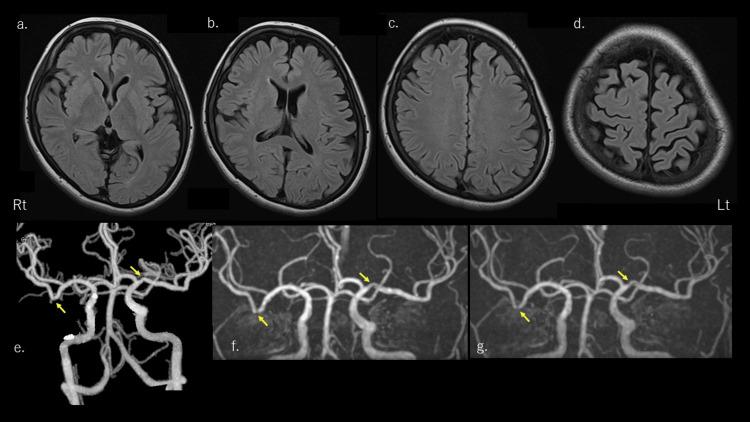

Migraine aura status (MAS) is a rare complication of migraine and is listed in the appendix of the International Classification of Headache, Third Edition. MAS occurs in migraine with aura (MwA) patients, with at least three auras occurring over a period of three days. We describe a case of MAS associated with a patient who had a migraine with a typical aura without headache (TAWH). She has experienced only visual auras, including periods of MAS complications, and has not experienced headaches or other auras, including sensory, speech, and motor. The patient is a 45-year-old woman. She had discomfort with visual aura without a headache every two to three months. The visual aura began to gradually darken a portion of the right side of the visual field binocularly, which gradually expanded around it and was surrounded by iridescent flashes running in a zig-zag pattern to the periphery. The area of the visual field abnormality gradually decreased and disappeared after approximately 15 minutes. One day, she had an aura once after dinner, and when she awoke without any trigger after going to bed, the aura appeared and repeated approximately three times. She experienced three to four auras the next day and the day after. In the six-month follow-up period, there was no further recurrence of MAS. Most previous reports of MAS have been associated with typical MwA, and there have been few other reports of MAS associated with TAWH as far as we could investigate.

偏头痛性眩晕状态(MAS)是偏头痛的一种罕见并发症,被列入《国际头痛分类第三版》附录中。MAS发生于有先兆偏头痛(MwA)患者中,在三天内至少出现三次先兆。我们描述了一例与一名有典型无头痛性先兆偏头痛(TAWH)患者相关的MAS病例。她仅经历过视觉先兆,包括MAS并发症发作期,未经历过头痛或其他先兆,如感觉、言语和运动性先兆。该患者为一名45岁女性。她每两到三个月会出现一次无头痛的视觉先兆不适。视觉先兆开始时双眼右侧视野的一部分逐渐变暗,其周围逐渐扩大,并被呈之字形向周边延伸的彩虹色闪光所环绕。视野异常区域在大约15分钟后逐渐缩小并消失。一天,她晚饭后出现了一次先兆,上床睡觉后无任何诱因醒来时,先兆再次出现并重复了约三次。第二天和第三天她又经历了三到四次先兆。在六个月的随访期内,MAS未再复发。既往大多数关于MAS的报道都与典型的MwA相关,就我们所能查到的而言,很少有其他关于与TAWH相关的MAS报道。